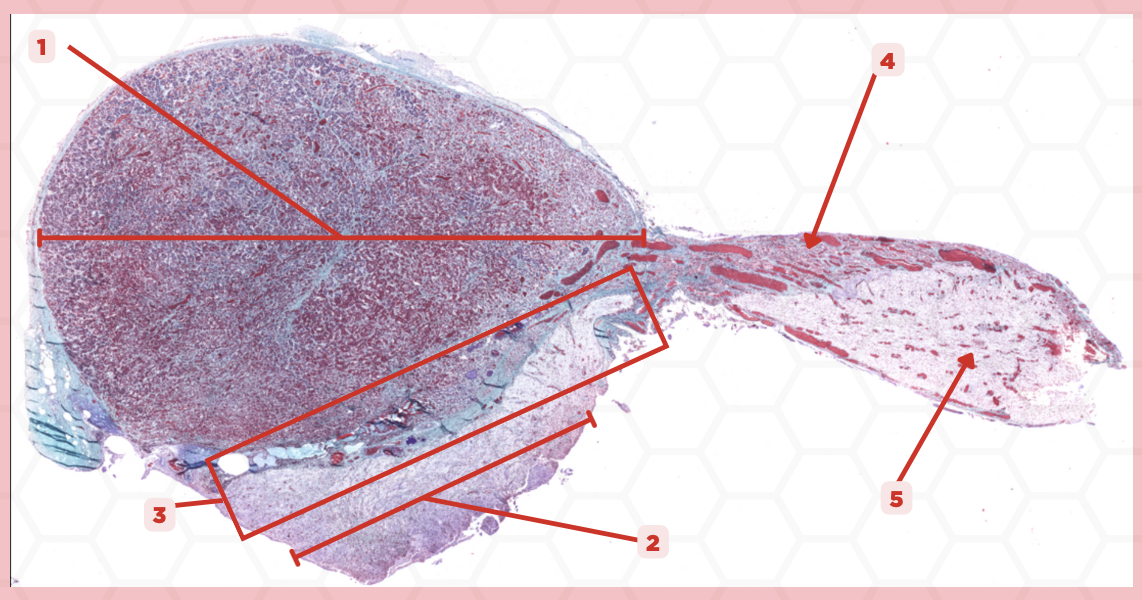

Adenohypophysis

What does #1, #4, and #5 form?

Pituitary

Identify the specimen.

Intermediate Lobe

Identify the structure labeled as 1.

Posterior Lobe

Identify the structure labeled as 2.

Pituitary Stalk

Identify the structure labeled as 3.

Pars Tuberalis

Identify the structure labeled as 4.

Anterior Lobe

Identify the structure labeled as 5.

Neural Ectoderm

What ectoderm is #2  derived from?

Oral Ectoderm

What ectoderm #1, #3, & #4 derived from?